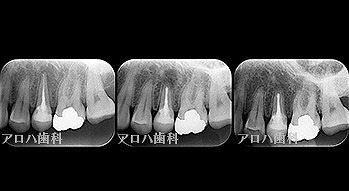

透過像が消失したケース

case1

初回根管治療

1年予後

治療回数1回

case2

左の透過像の変化(5年予後)

(のちに右も壊死により根管治療)

case3

再根管治療

瘻孔の消失